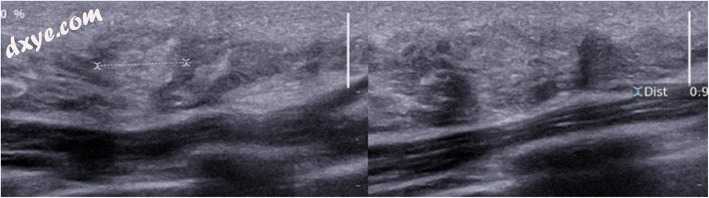

腺病

腺病对应于末端导管小叶单元(上皮细胞,肌上皮细胞和结缔组织)的所有成分的增生,导致小叶的大小和数量增加。 腺病可以临床上以缓慢增长的乳房肿胀的形式存在。 在大多数情况下,它与任何乳房X线照片标志无关。 花粉腺病可呈现多微结构性射线照片外观。 也可以观察到点状微钙化。 在超声检查中,腺病是一个可变回声区,可能有不规则的边缘(图13)。

图13

腺病。 45岁女性右乳房内部肿胀直径15毫米,对应于与点状微钙化相关的乳房X线不透明度差,在4年内发展缓慢。超声:混合回声区,主要是高回声区,长轴平行于皮肤,不改变超声波束